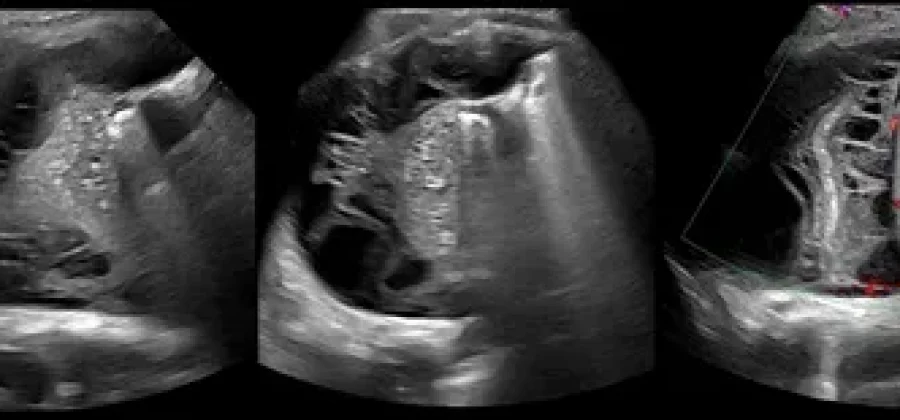

• Обнаружить даже небольшое количество жидкости (плевральный выпот).

• Определить характер этой жидкости (например, транссудат или экссудат).

• Выявить уплотнения, опухоли, спайки или другие патологические изменения.

• Диагностика плеврального выпота. УЗИ не только подтверждает наличие жидкости, но и помогает оценить ее объем и структуру.

• Определение причины выпота. По характеристикам жидкости на УЗИ врач может предположить, вызвана ли она воспалением, сердечной недостаточностью, опухолью или инфекцией (например, при пневмонии).

• Дифференциальная диагностика. Помогает отличить жидкость от других патологий, например, утолщения плевры или опухоли.